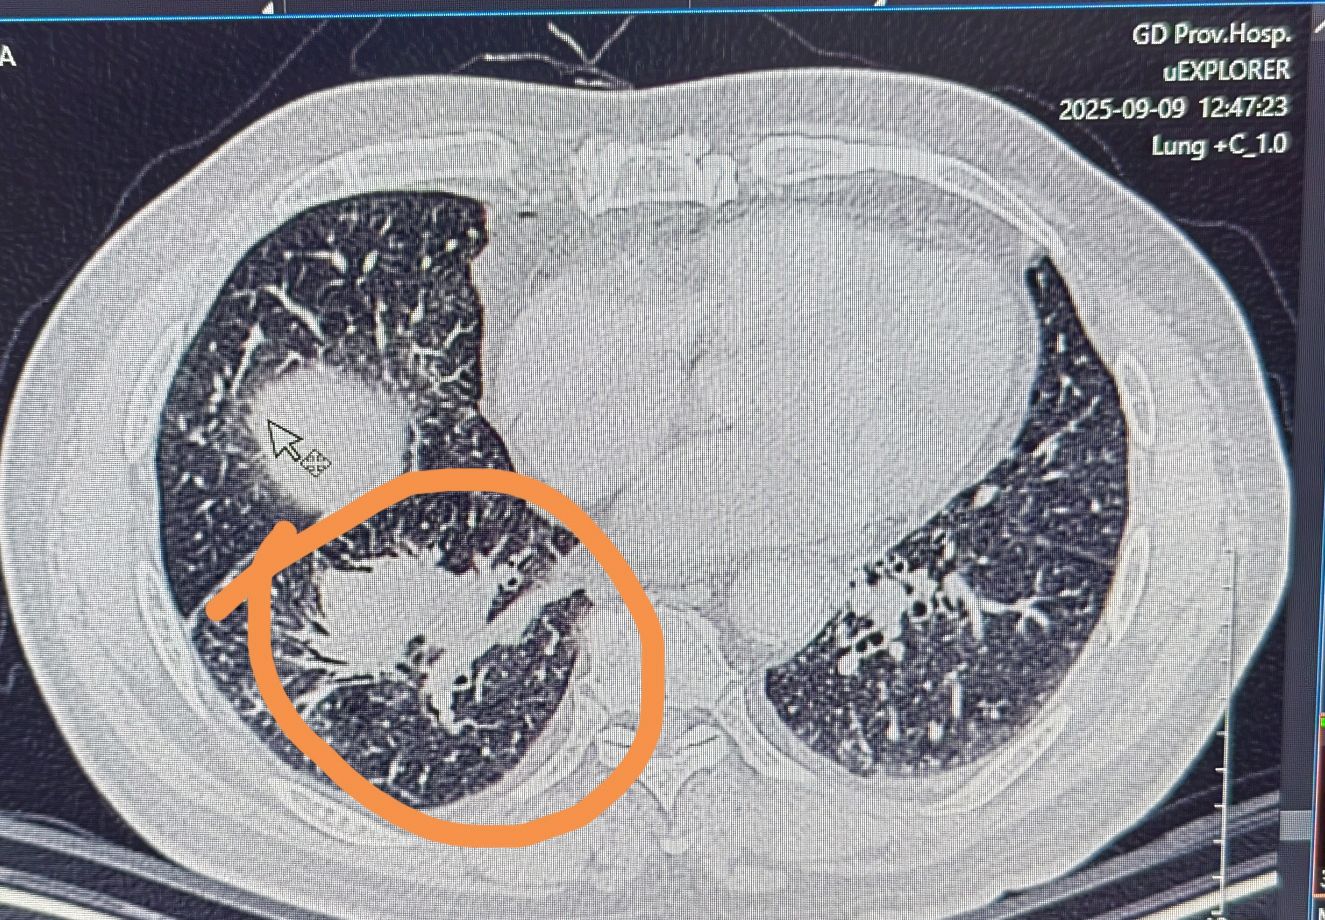

局部晚期肺癌经过化疗联合免疫治疗后一年手术

新辅助治疗后手术切除——中晚期肺癌患者的机遇